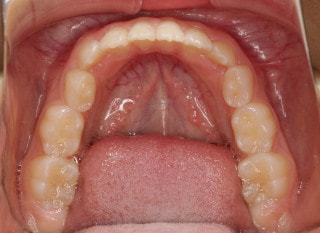

小児期の第二段階

終了時